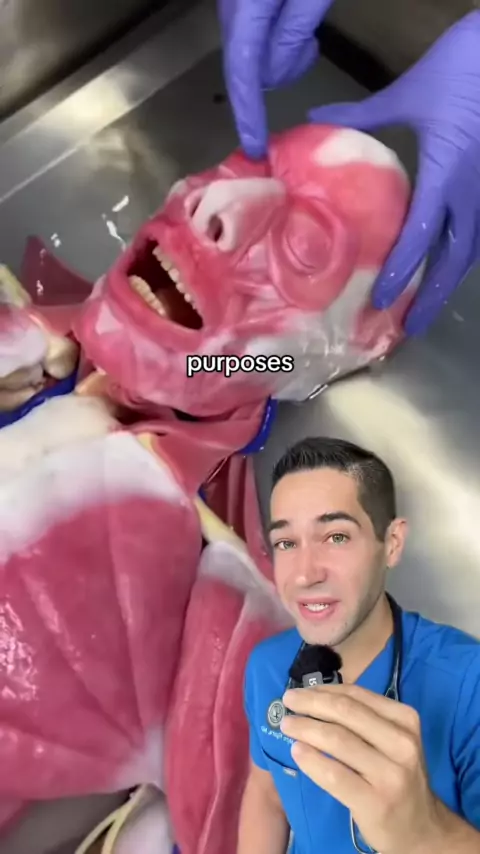

Você compraria um? # cadaver # syntheticcaver # doctor # anatomy # premed # medicine # medschool

2